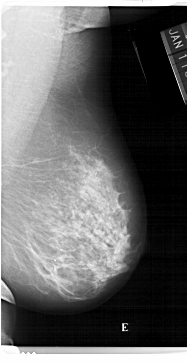

A_1230_1.LEFT_CC

LEFT_CC LINES 6661 PIXELS_PER_LINE 3391 BITS_PER_PIXEL 12 RESOLUTION 43.5 NON_OVERLAY